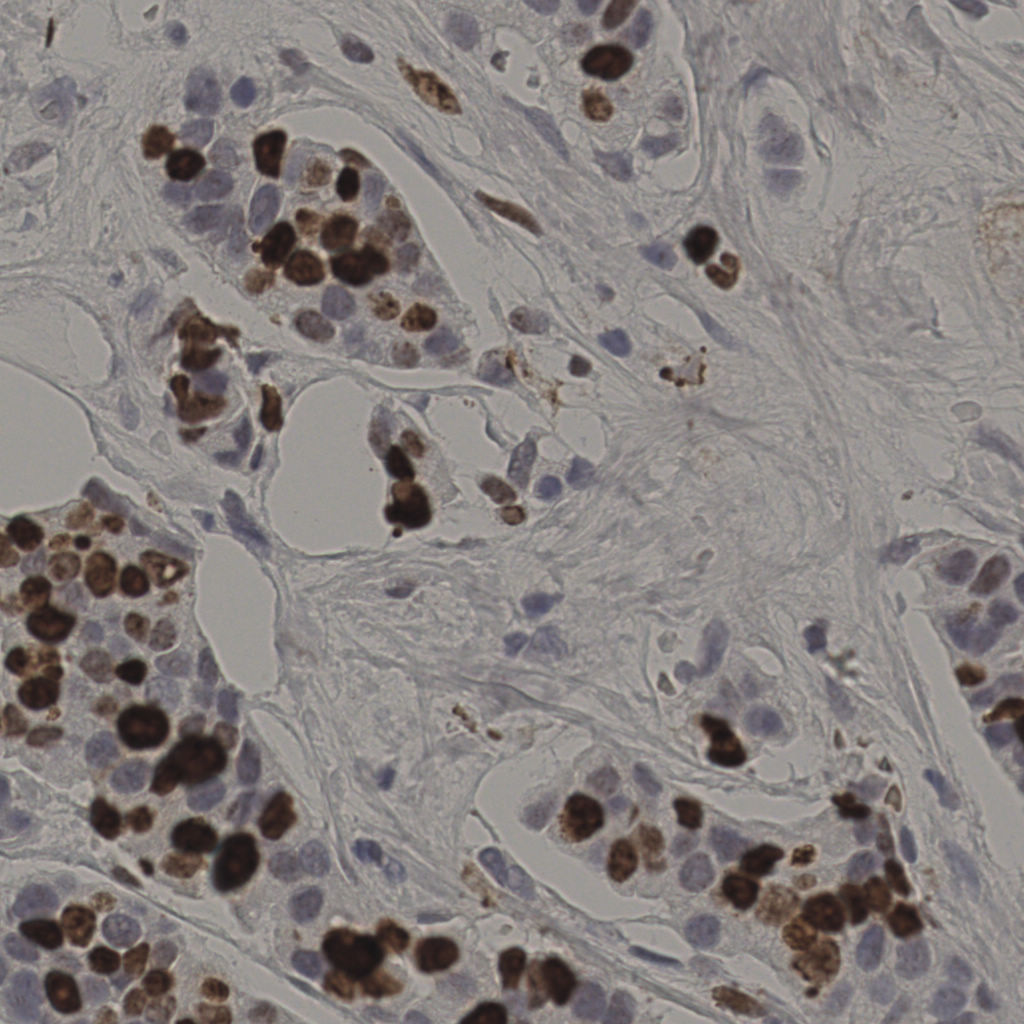

17.75%

Ki67 指数

阴 7986

阳 1723